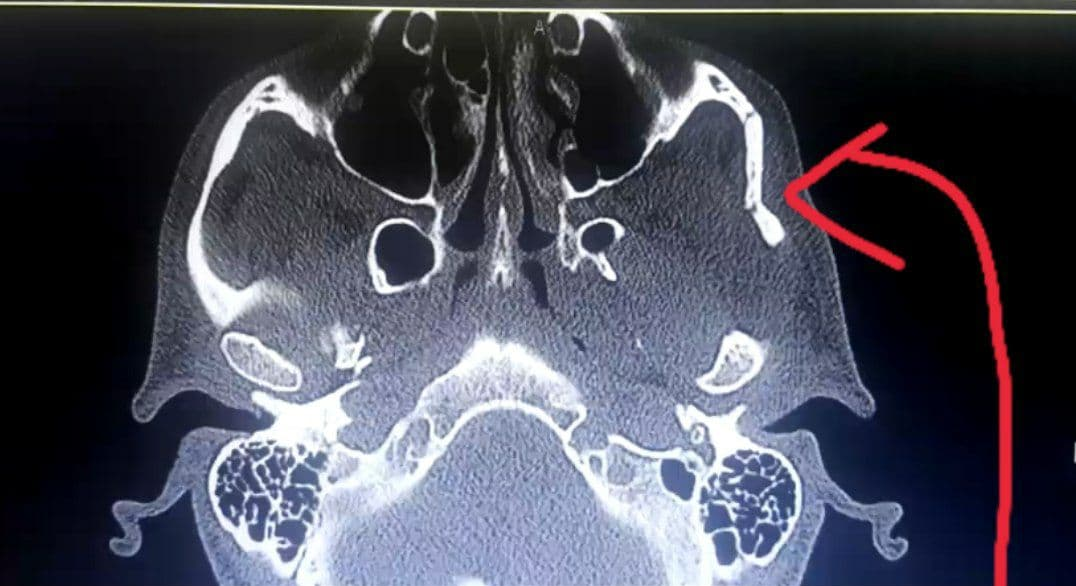

حسین پورامینی در دقیقه 30 این بازی به دلیل بر اثر برخورد آرنج نیما انتظاری از ناحیه جمجمه دچار شکستگی شد.

بر اساس اعلام دکتر صبا صابری، پزشک تیم پیکان این بازیکن پس از رادیولوژی امروز جراحی کوچکی امروز انجام میدهد و با کردن دوران نقاهت مشکلی برای حضور در دیدار بعدی شاگردان مهدی تارتار با نساجی ندارد.